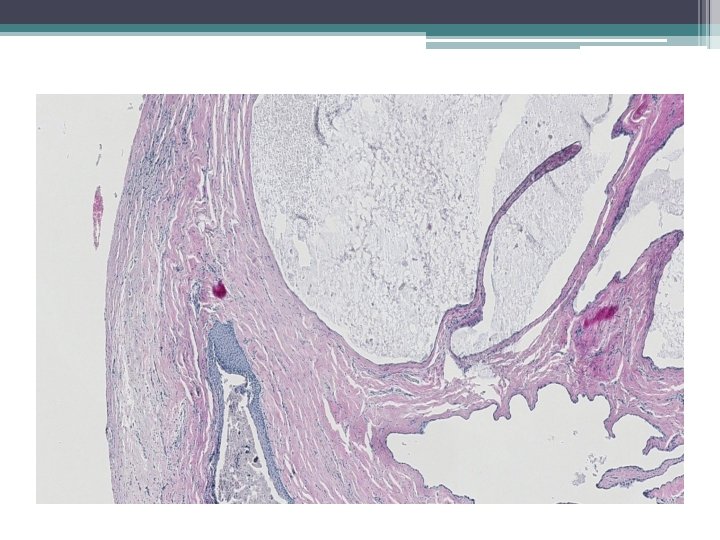

Mikro:

Ektopická prostatická tkáň • • vzácně lokalizace: cervix, vagína věk 21 -65 let mikroskopicky : tubuly a aciny některé papilární, některé kribriformní, s dlaždicovou metaplázií

• Mikroskopicky: • dobře ohraničená hnízda s vrstevnatým dlaždicovým epitelem a tubuly vystlané jednou až dvěma řady kubických buněk, nebo dlaždicovými buňkami. V centru hnízd může byť přítomná nekróza s kalcifikací, nebo keratinové perly.